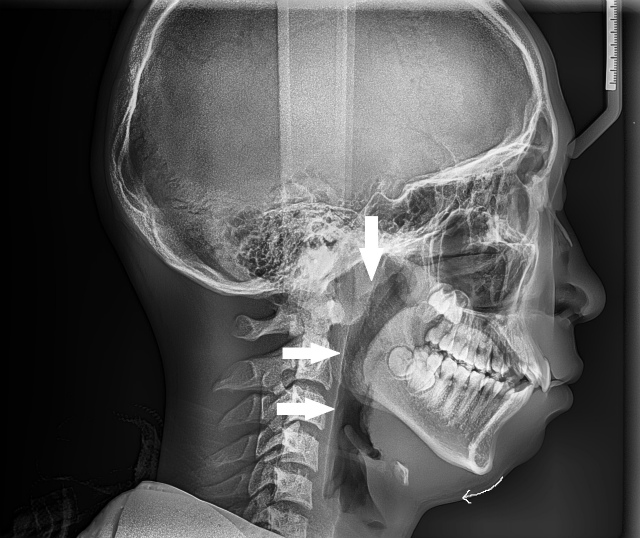

一番上の矢印は咽頭扁桃(アデノイド)が腫れている箇所を示している。下の矢印は口蓋扁桃の腫脹により舌が押されて特に気道が狭くなっている箇所 (10代前半女性)